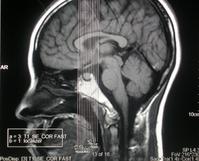

臨床表現為視力視野障礙,影像學檢查可見鞍區病變,蝶鞍骨質變化。如有內分泌表現診斷一般不難,需和顱咽管瘤、腦膜瘤、動脈瘤等鑑別,MRI對發現微腺瘤很有意義。

垂體瘤診斷方面,影像學檢查是非常重要的手段。其中以鞍區的核磁共振(MRI)檢查對垂體瘤的檢出率最高。通過鞍區薄層(每1mm掃描一層)增強影像的MRI檢測,若結合動態造影MRI檢測,直徑小至2-3mm的垂體微腺瘤也可以顯像。鞍區增強CT顯像對於部分垂體大腺瘤顯像效果好,可以了解鞍底骨質的破壞程度以及蝶竇氣化的程度。